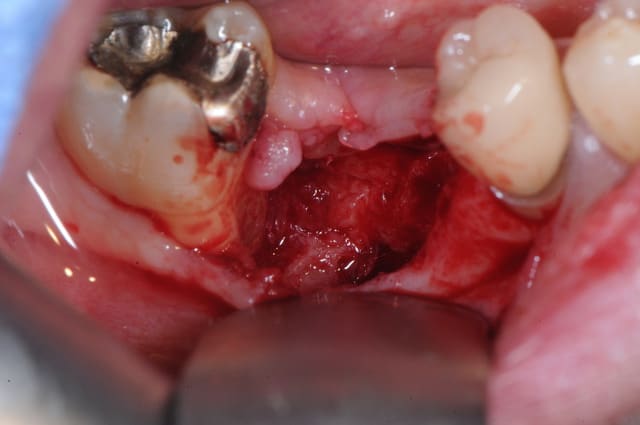

patient qui consulte lundi dernier pour avis implantaire pour 46

je regarde et je vois un petit morceau osseux bien vilain qui dépasse.

l'extraction a eu lieu il y a 4 mois par un confrère qui bosse bien et donc je ne remet pas en cause ses compétences.

l'extraction s'est pourtant bien déroulée et d'après le patient, les suites aussi. là j'en doute un peu plus mais bon...

je lui ai programmé rapidement une intervention pour ce matin afin de cureter.

il a simplement fallu tirer un peu sur le séquestre